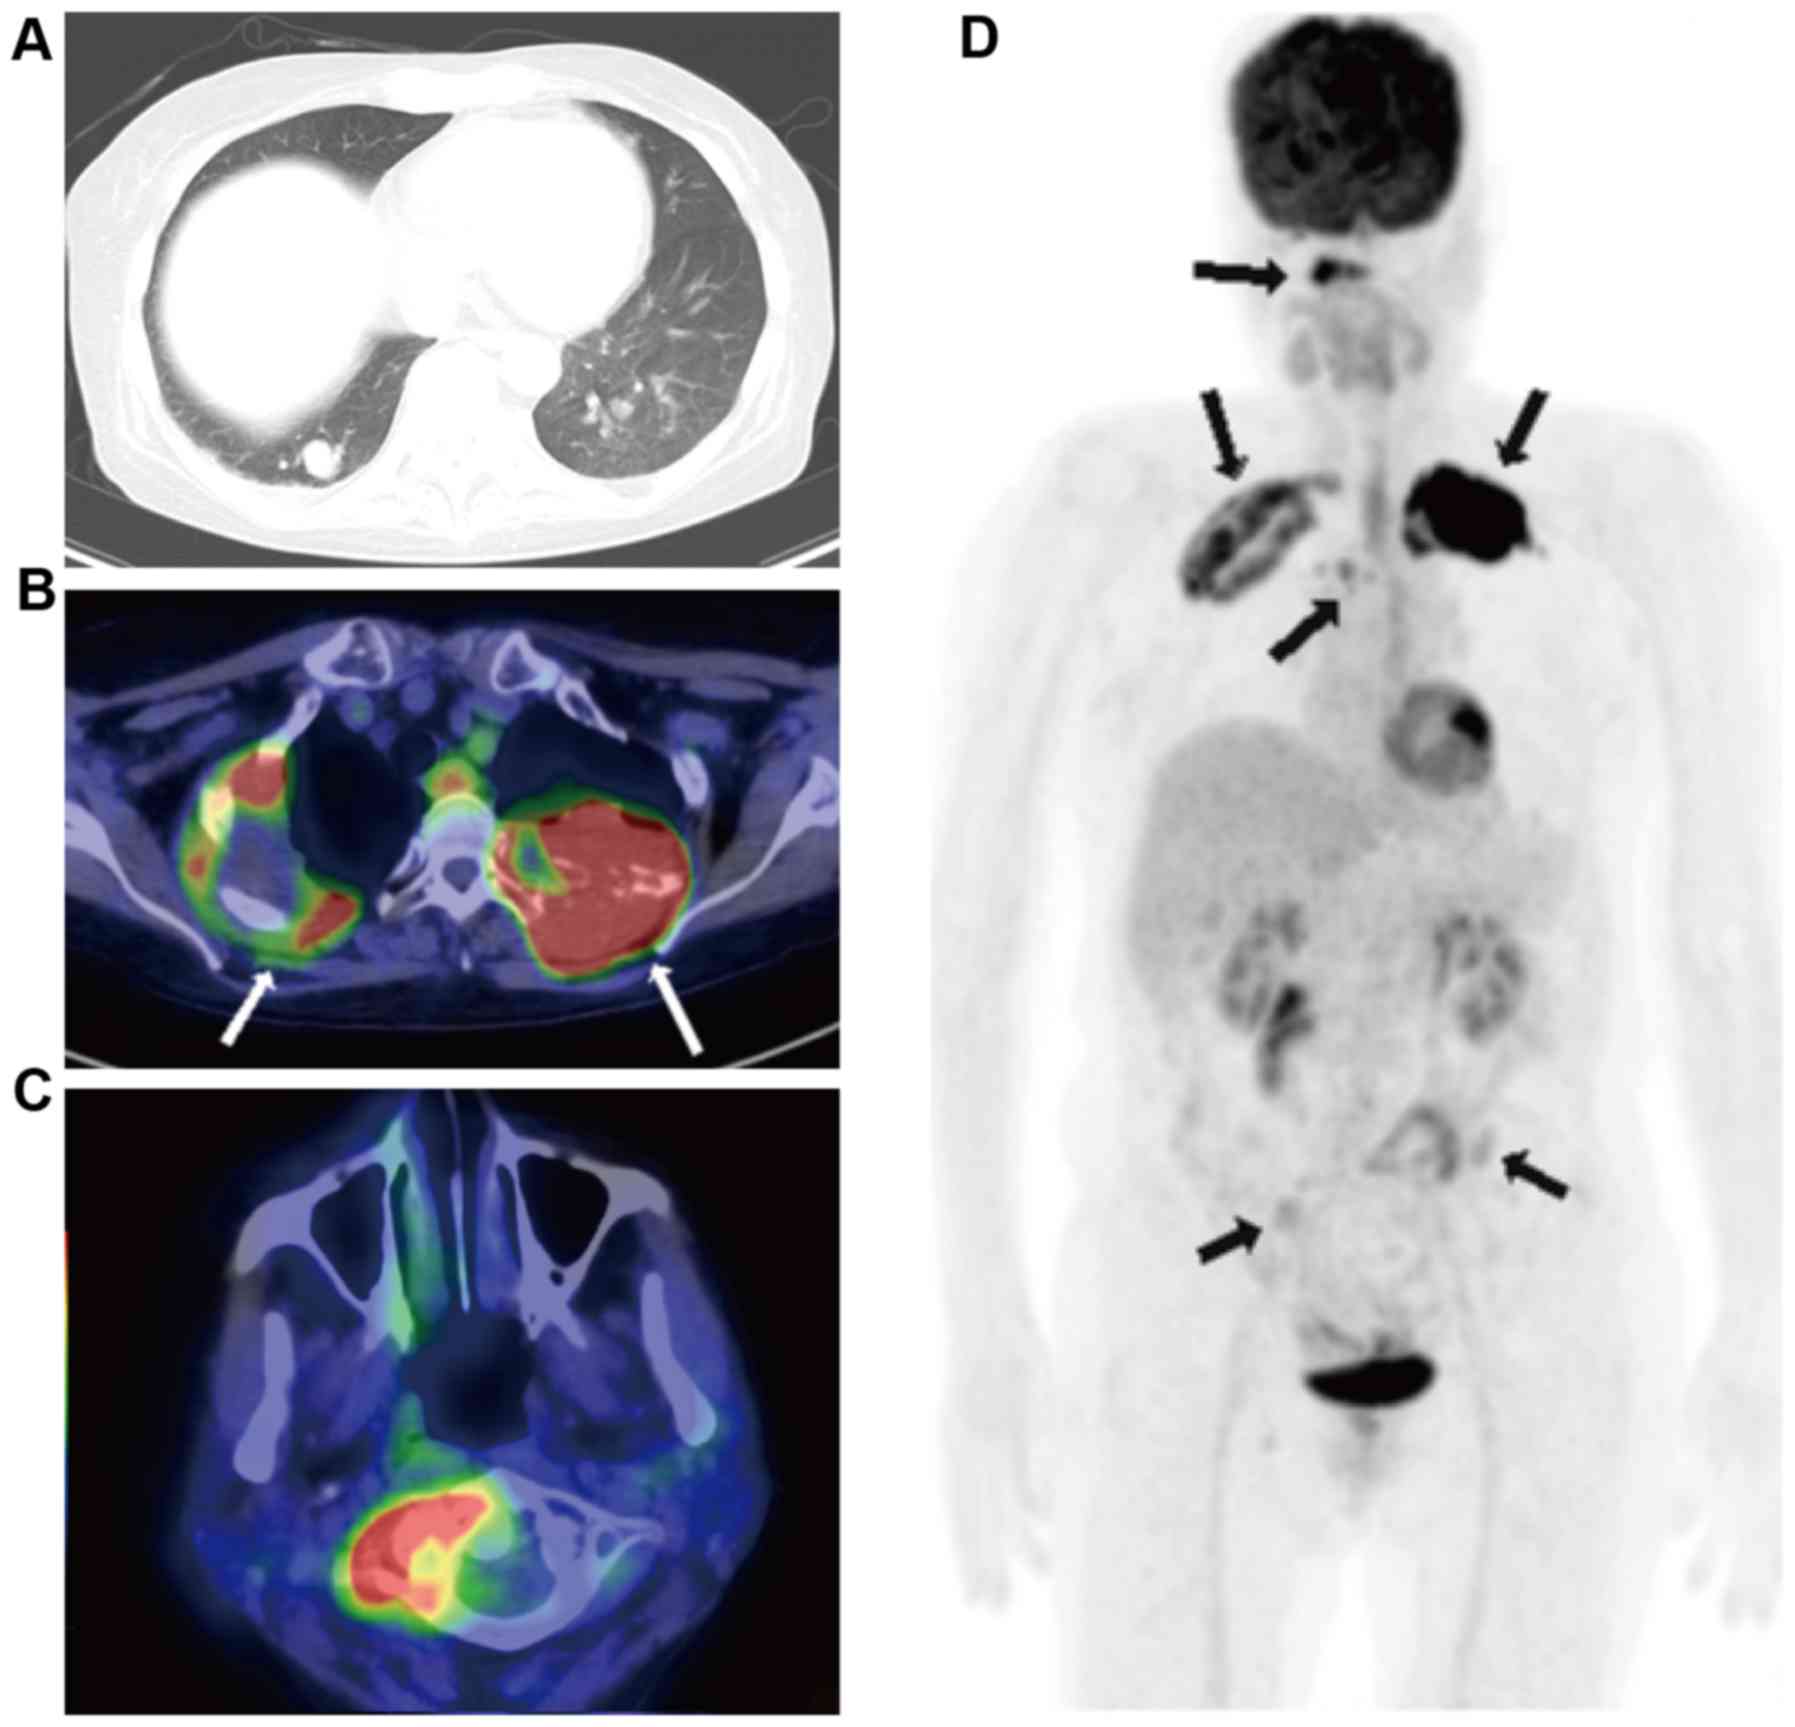

A 38-year-old female was diagnosed with papillary adenocarcinoma of the thyroid gland following a fine-needle aspiration biopsy in Kansai Medical University Takii Hospital in July 2009. However, a CT scan of the chest revealed the presence of multiple nodules of varying sizes in each of the lungs (Fig. 1A). Consequently, an 18-FDG-PET/CT scan was performed. A lesion with high 18-FDG uptake [maximum standard uptake value (SUVmax), >4.9] was observed in the left lobe of the thyroid gland (Fig. 1B and C). However, the results revealed that none of the pulmonary nodules demonstrated 18-FDG uptake (SUVmax, <1.6; Fig. 1C and D). To elucidate whether the pulmonary nodules were metastatic, a CT-guided needle biopsy of the lungs was performed.

Figure 1.

Radiological findings for case 1. (A) CT scan of the pulmonary nodule. (B) A lesion exhibiting high 18-FDG uptake (SUVmax, >4.9) was detected in the tumor of the left lobe of the thyroid gland (arrow). (C) The fusion image of 18-FDG-PET/CT in the coronal plane. Only one lesion in the thyroid gland exhibited a positive accumulation of 18-FDG (arrow). (D) The fusion image of 18-FDG-PET/CT in the horizontal plane. The pulmonary nodule demonstrated no significant 18-FDG uptake (SUVmax, <1.6). CT, computed tomography; 18-FDG-PET/CT, 2-deoxy-2-(fluorine-18)-fluoro-D-glucose positron emission tomography/CT; SUVmax, maximum standard uptake value.